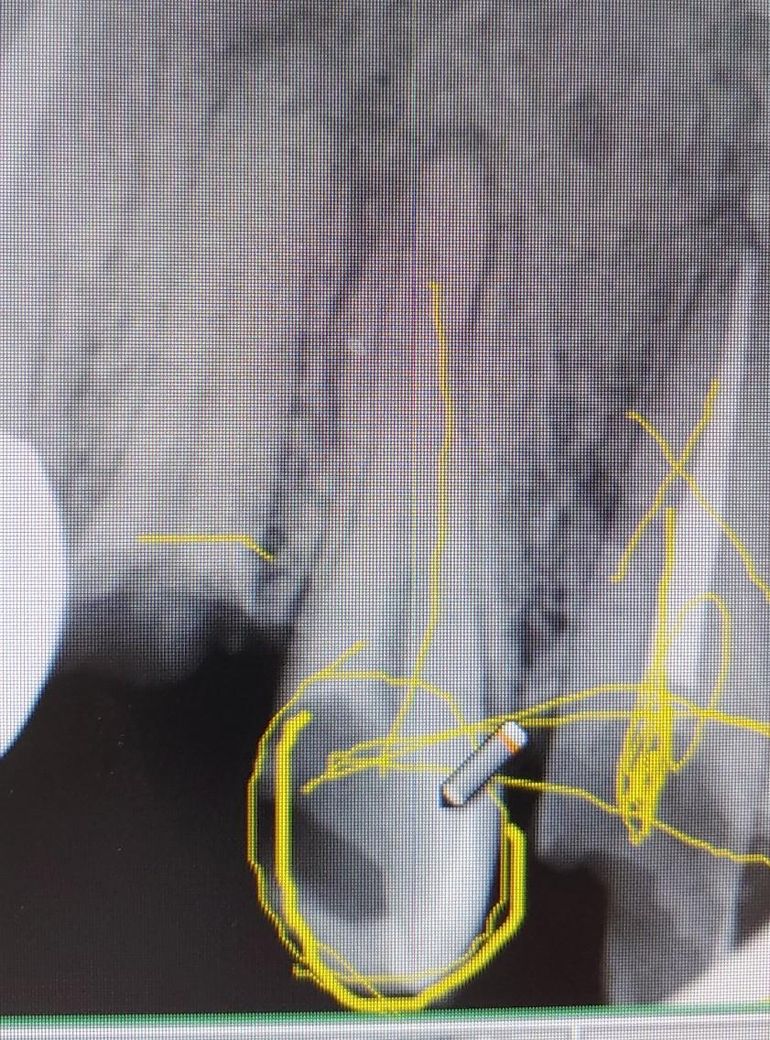

윗쪽 작은어금니 꼭 신경치료 해야할까요?

안녕하세요 제가 오른쪽 윗 작은어금니가 예전부터 충치가 있었는데 충치로 인해 약간 깨져있는 상태인데 혹시 신경치료 없이 충치부분만 제거하고 인레이나 크라운으로 씌워서 사용할 수는 없을까요?

• 1번 째 사진

충치의 범위를 봤을 대엔 신경치료를 해야할 가능성이 매우 높습니다. 충치를 제거해봐야 확실히 알 수 있습니다.

치아가 많이 깨진상태이신거 같은데 저정도면 신경치료를 하시고 크라운 치료까지 하셔야될것같습니다.